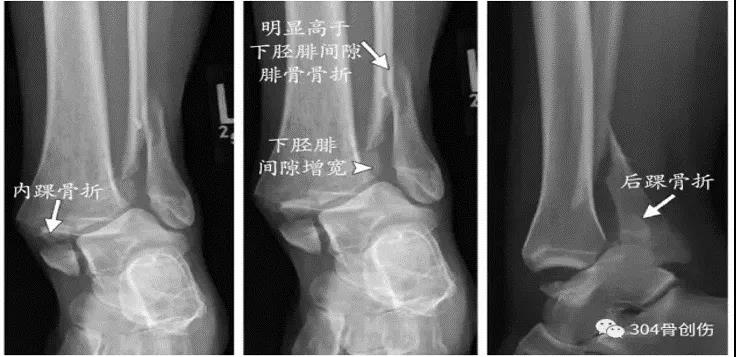

Lauge-Hansen-旋前外旋(PE)受伤时,足处于旋前背伸外展位,距骨外旋。Ⅰ:三角韧带紧张,造成三角韧带损伤或者是内踝撕脱性骨折。Ⅱ°:外力继续作用,距骨外旋造成下胫腓前韧带和骨间韧带损伤,或者韧带附着点撕脱性骨折。Ⅲ°:外力继续作用,腓骨受到向外向后的旋转应力,造成腓骨的螺旋性骨折(特点:腓骨由于足本身的位置,外旋力大,向上传导,骨折位于下联合上方,甚至可以达到腓骨颈部位- Maisonneuve骨折)。Ⅳ:外力继续作用,下胫腓后韧带紧张,造成下胫腓后韧带断裂或后踝撕脱骨折。